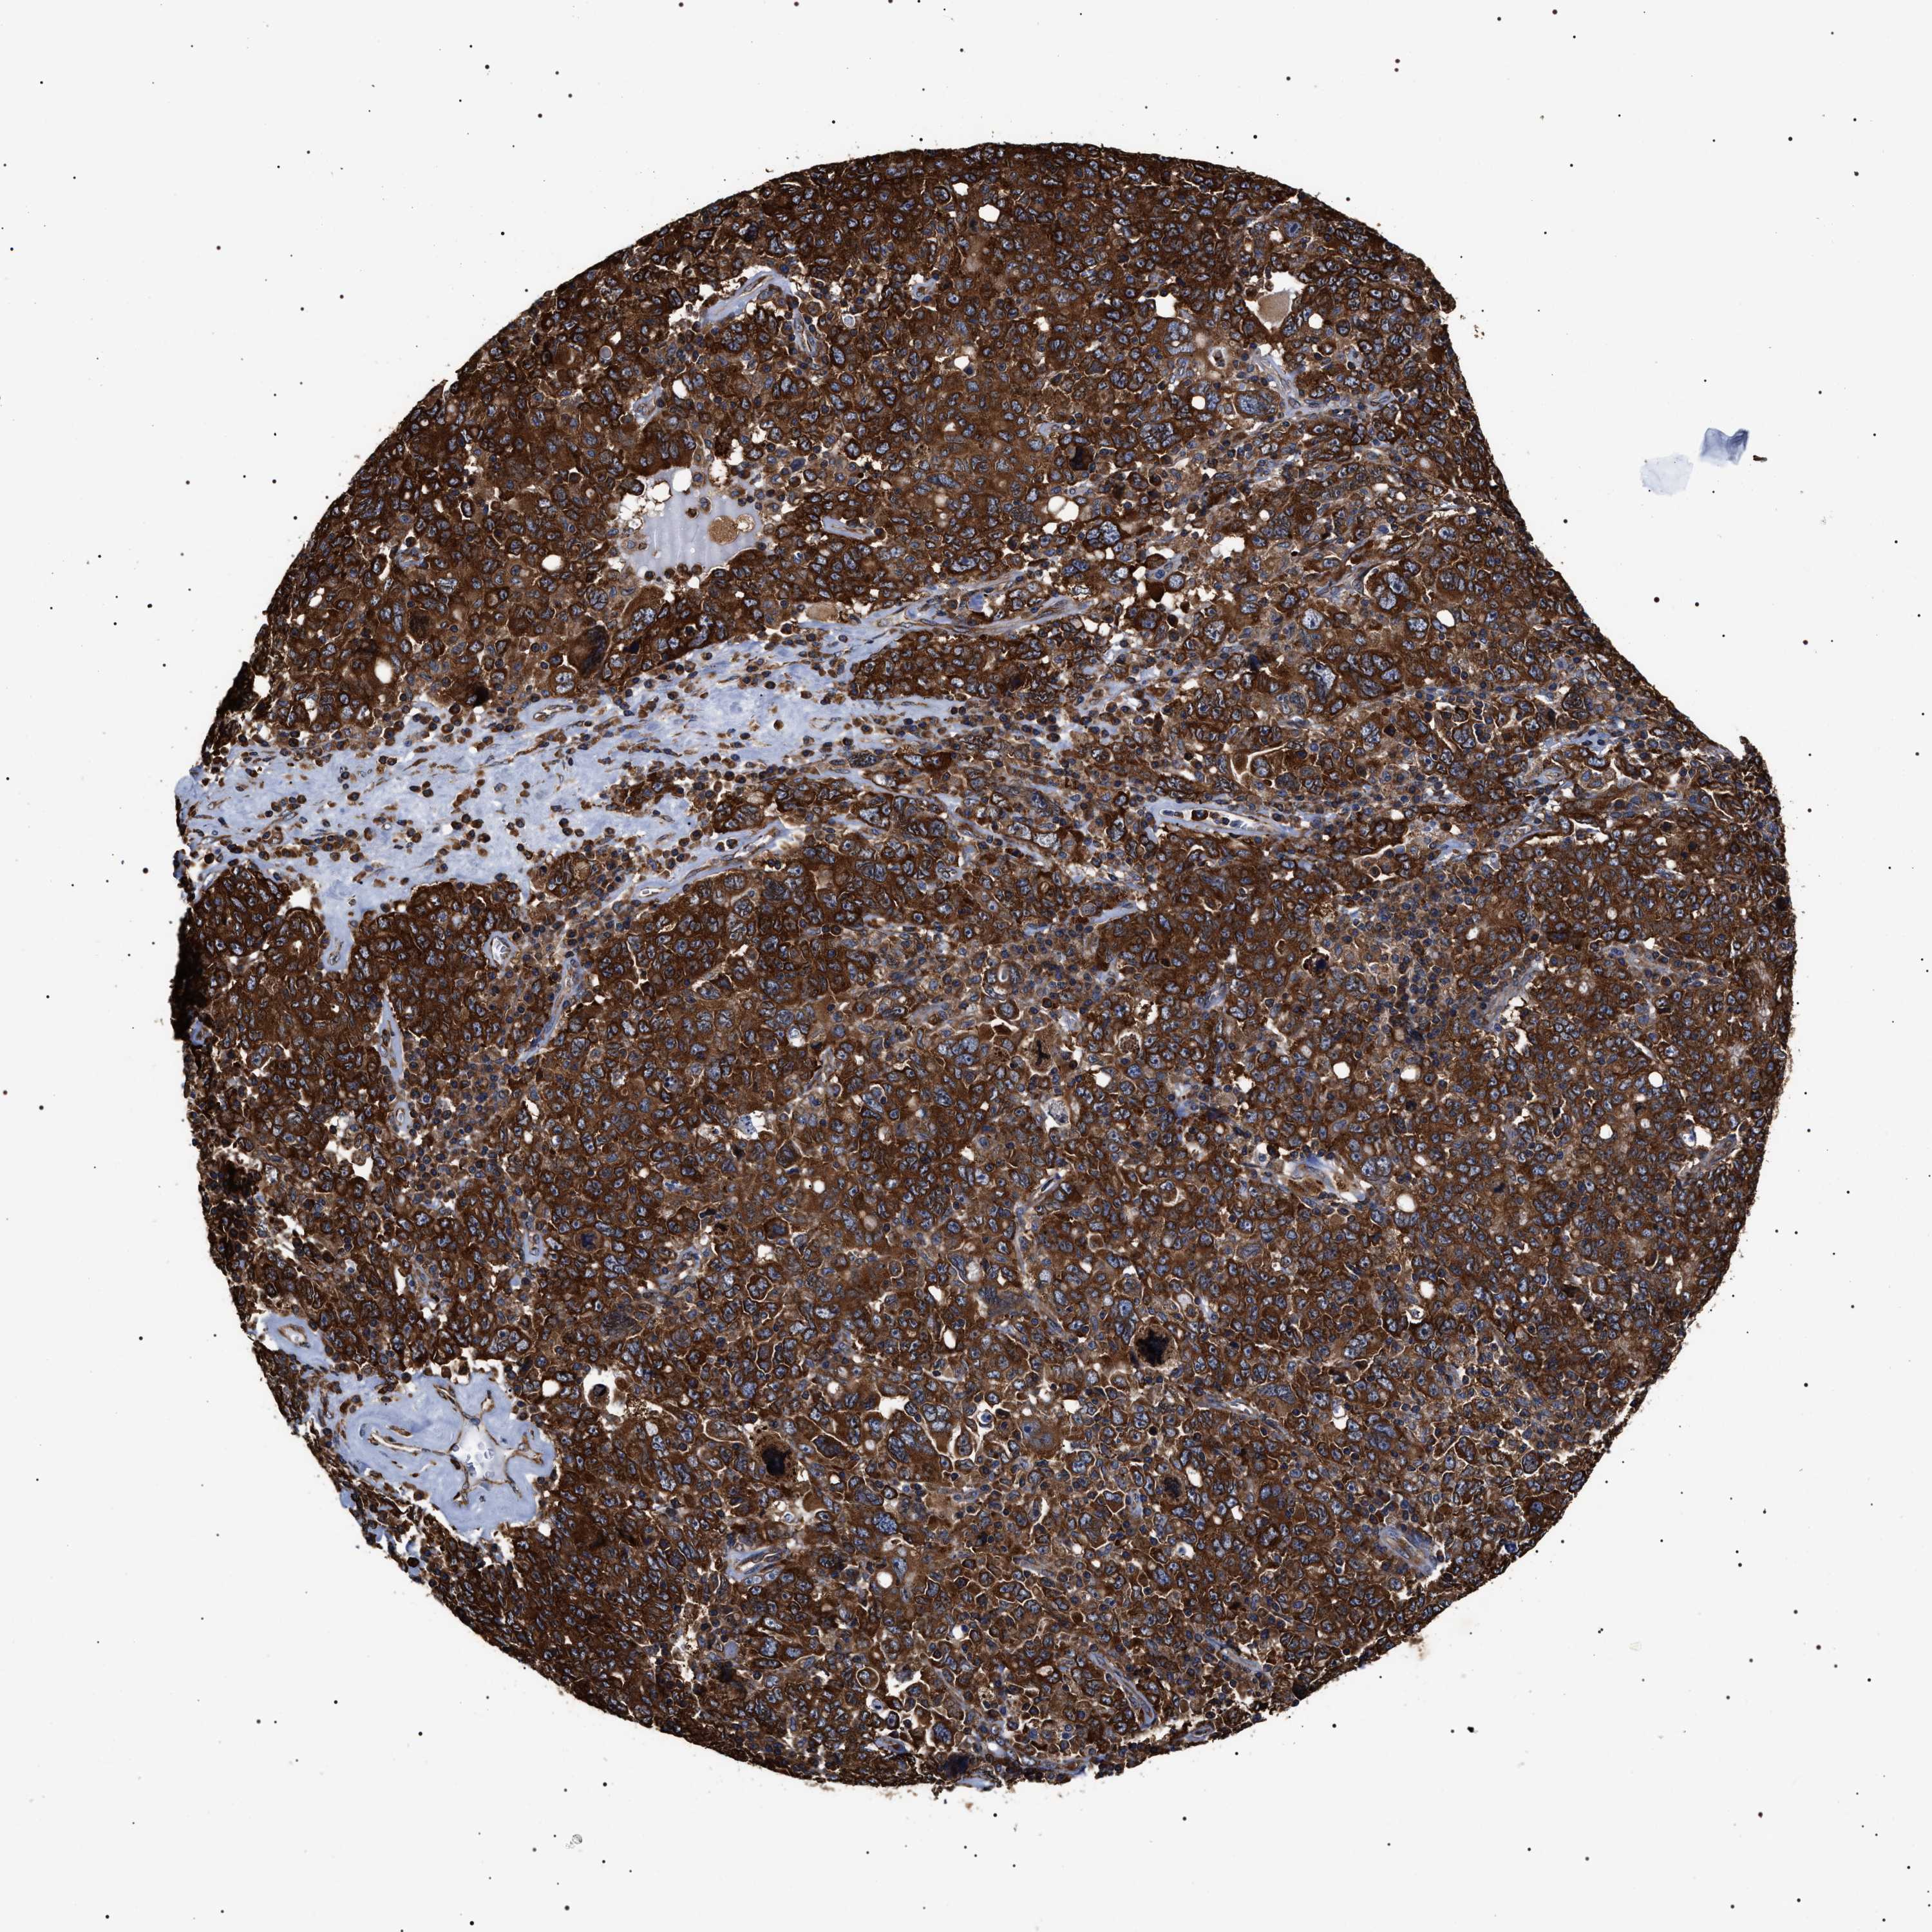

OVARIAN CANCER - Protein expressioni

A mouse-over function shows sample information and annotation data. Click on an image to view it in a full screen mode. Samples can be filtered based on level of antibody staining by selecting one or several of the following categories: high, medium, low and not detected. The assay and annotation is described here.

Note that samples used for immunohistochemistry by the Human Protein Atlas do not correspond to samples in the TCGA dataset.

Antibody stainingi

Antibody staining in the annotated cell types in the current human tissue is reported as not detected, low, medium, or high, based on conventional immunohistochemistry profiling in selected tissues. This score is based on the combination of the staining intensity and fraction of stained cells.

Each image is clickable and will lead to virtual microscopy that enables deeper exploration of all samples and also displays staining intensity scores, fraction scores and subcellular localization as well as patient and tissue information for each sample.

Antibody HPA020559

Antibody CAB026297

Staining

High

Cystadenocarcinoma, serous, NOS